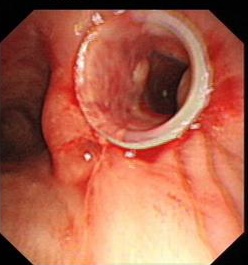

近日,我科成功为一右侧主支气管狭窄患者放置硅酮支架,解决患者多年气促烦恼。该患者为河南人,长期在宁波打工,自幼有气促病史,但能胜任一般体力活动,当时患者未予重视治疗。近年来,患者症状不断加重,稍活动即气促明显,为求诊治,至我院呼吸科门诊,当时经支气管镜检查确诊为右主支气管狭窄,考虑既往陈旧性支气管结核肉芽肿,疤痕形成所致。我科呼吸介入小组曾多次对患者病灶进行消融,球囊扩张等治疗,效果均不理想,该患者右主支气管狭窄处肉芽肿反复增生复发,气促症状反复发生。在俞万钧副院长组织下,我科进行多次全科室讨论,制定了右侧主支气管放置硅酮支架的手术方案。因为该患者自幼气道狭窄,疤痕形成较长,气道结构发生改变,手术存在相当难度,极有可能硅酮支架放置失败。我科针对该患者制定一系列周密的术前,术中,术后应对方案。昨日俞万钧副院长亲自主刀,在硬质支气管镜下对患者右侧主支气管狭窄段进行消融,成功放置硅酮支架,术后患者症状完全消失,本周即可出院。自2年前硅酮支架进入中国,我科在硬质支气管镜下已为多位患者放置硅酮支架,解除患者痛苦。(徐涛)